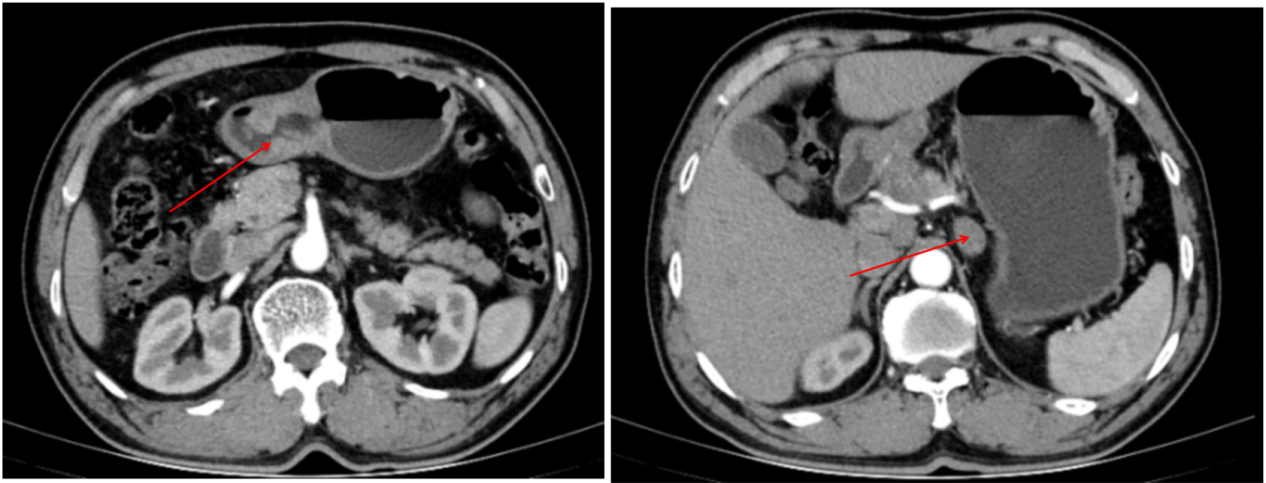

影像学检查(2022年6月13日):腹部CT增强扫描提示,胃部恶性肿瘤,伴胃窦周围淋巴结转移,最大淋巴结短径约22mm。

109.1.png

图1  腹部CT增强结果